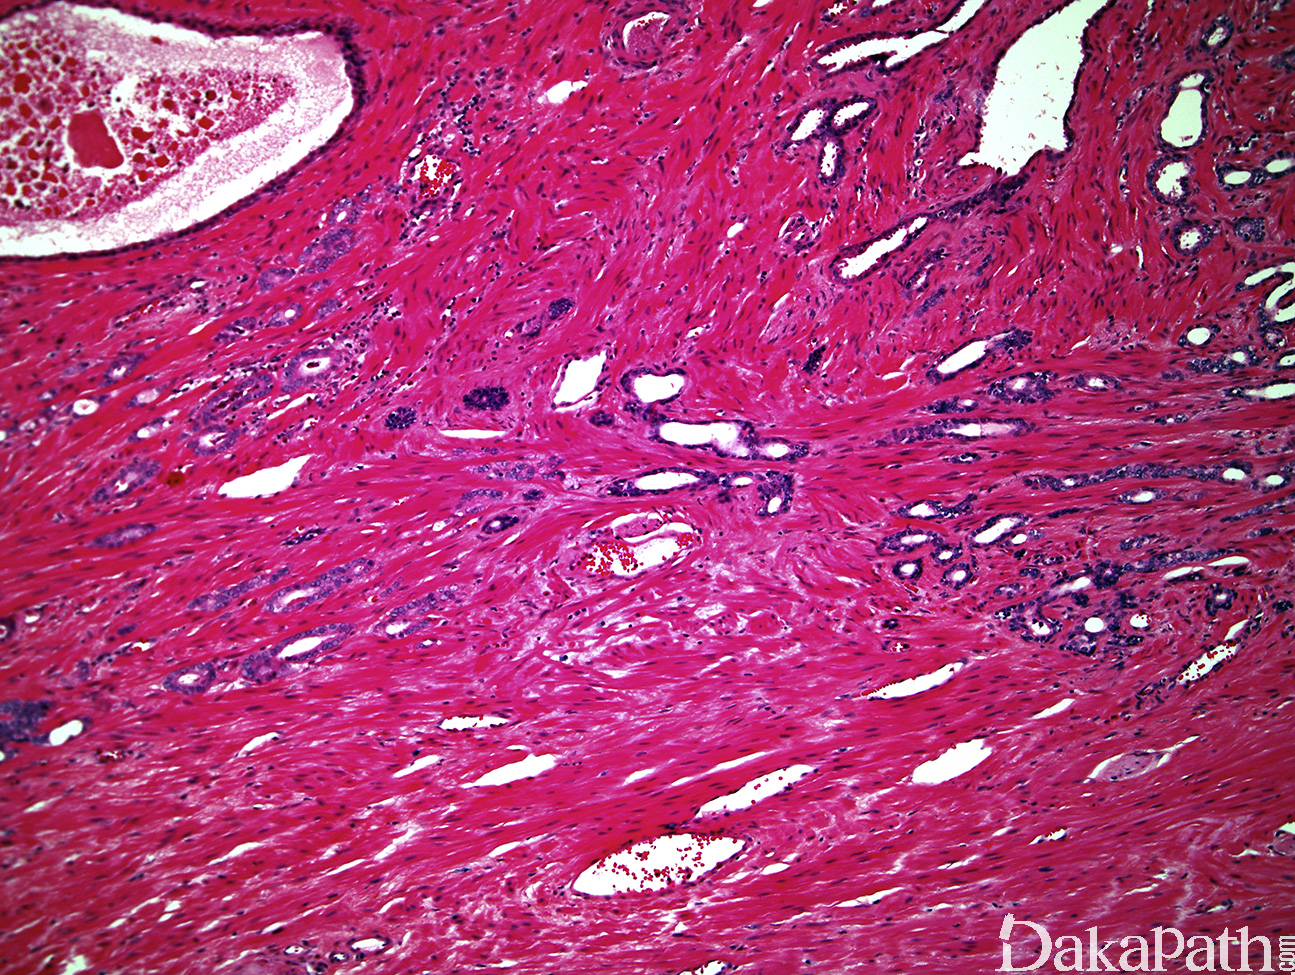

- 其特征是细胞缺乏部分胞浆,类似于前列腺萎缩,组织结构常呈 Gleason 3 级图像,由相互分离的单个腺体构成;

- 呈浸润性生长,可在大的良性腺体之间见到数个小的萎缩性腺体;

- 有时细胞核扁平,缺乏显著的核仁,与萎缩鉴别困难。